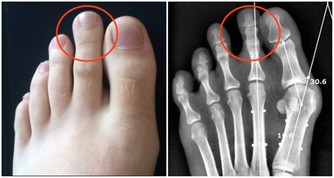

宿便的典型表現:天天排便仍有殘便感,或長期一周內持續 3 天以上不排便

「便秘」排便是人體排毒最重要的途徑,通常每天排便一次。如排便不規律,可能有便秘的情況,甚至排便間隔時間多於3天,說明你的腸道內留有宿便。

糞便留在腸道內,有害物質被再次吸收,可引起胃腸神經功能紊亂而致食欲不振、腸胃不適、腹部脹滿、口苦、肛門排氣多等表現,甚至可誘發結腸癌。